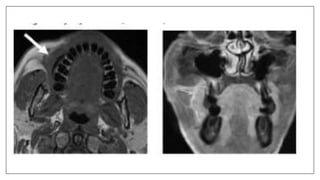

MRI in space infection

• Used in deep neck space infection: Retropharyngeal and Parapharyngeal